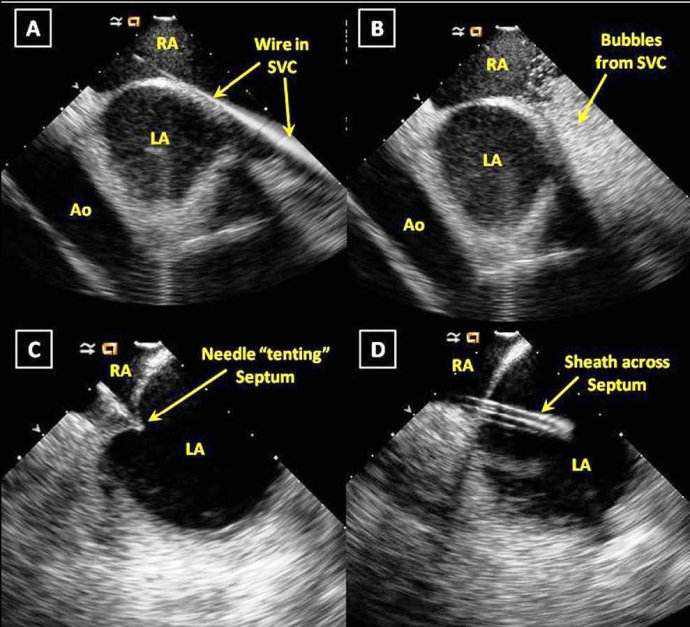

tee指导下完成房间隔穿刺

患者,男性,56岁,明确诊断为持续性房颤。入院后,心血管内科医务人员立即开展病情讨论,并制定详细周密的手术计划,同时在患者及其家属知情同意后,实施TEE指导下零射线房颤射频消融术。手术用时2小时,术中一切顺利,术后患者恢复良好,无不良反应。